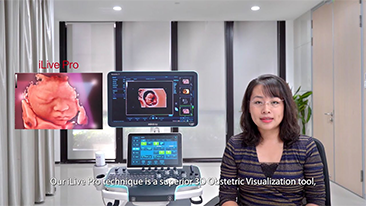

Con la tecnologĂa de la avanzada plataforma ZST+, las soluciones inteligentes completas de la serie Nuewa estĂĄn dise?adas especialmente para mejorar la salud de las mujeres durante el perĂodo previo al embarazo, el embarazo y la recuperaciĂłn en el posparto, con el fin de brindar diagnĂłsticos integrales y eficientes para enfrentar desafĂos clĂnicos cada vez mĂĄs exigentes.

Productos para la salud de la mujer